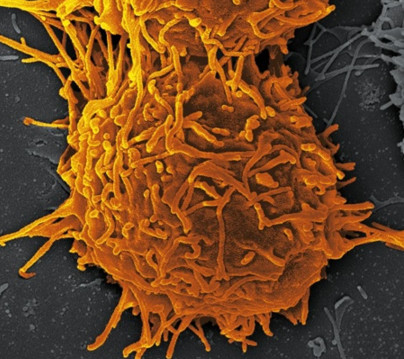

Фотографии опухоли медуллярной аденокарциномы

Раздел: Снимки-откровения